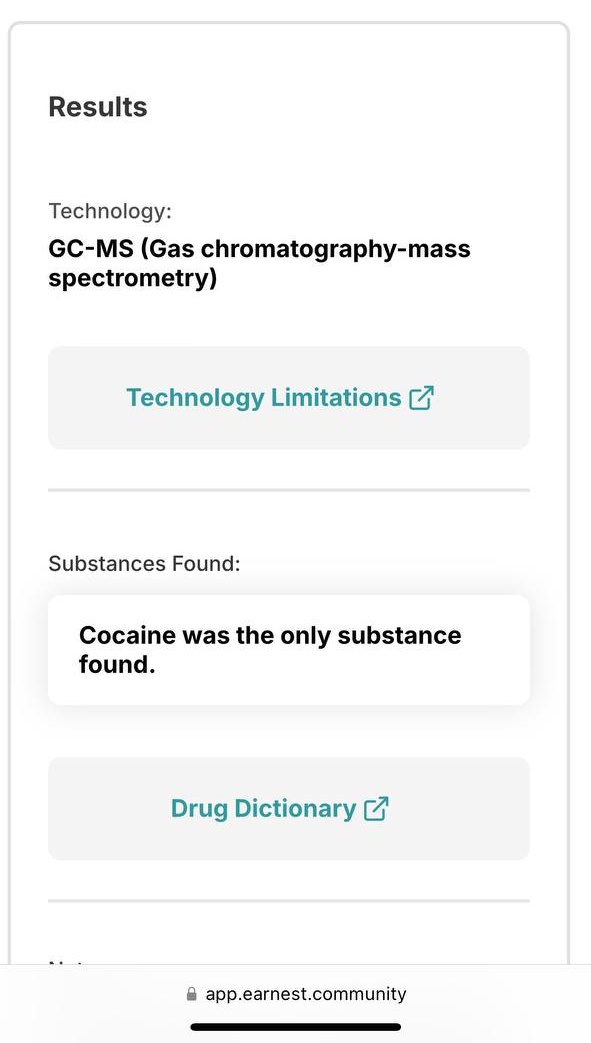

对于药物过量引起的中枢神经系统副作用,有一些不常见或常见的药物来控制症状。

评论区欢迎补充 https://t.co/7S4tGVDEM5